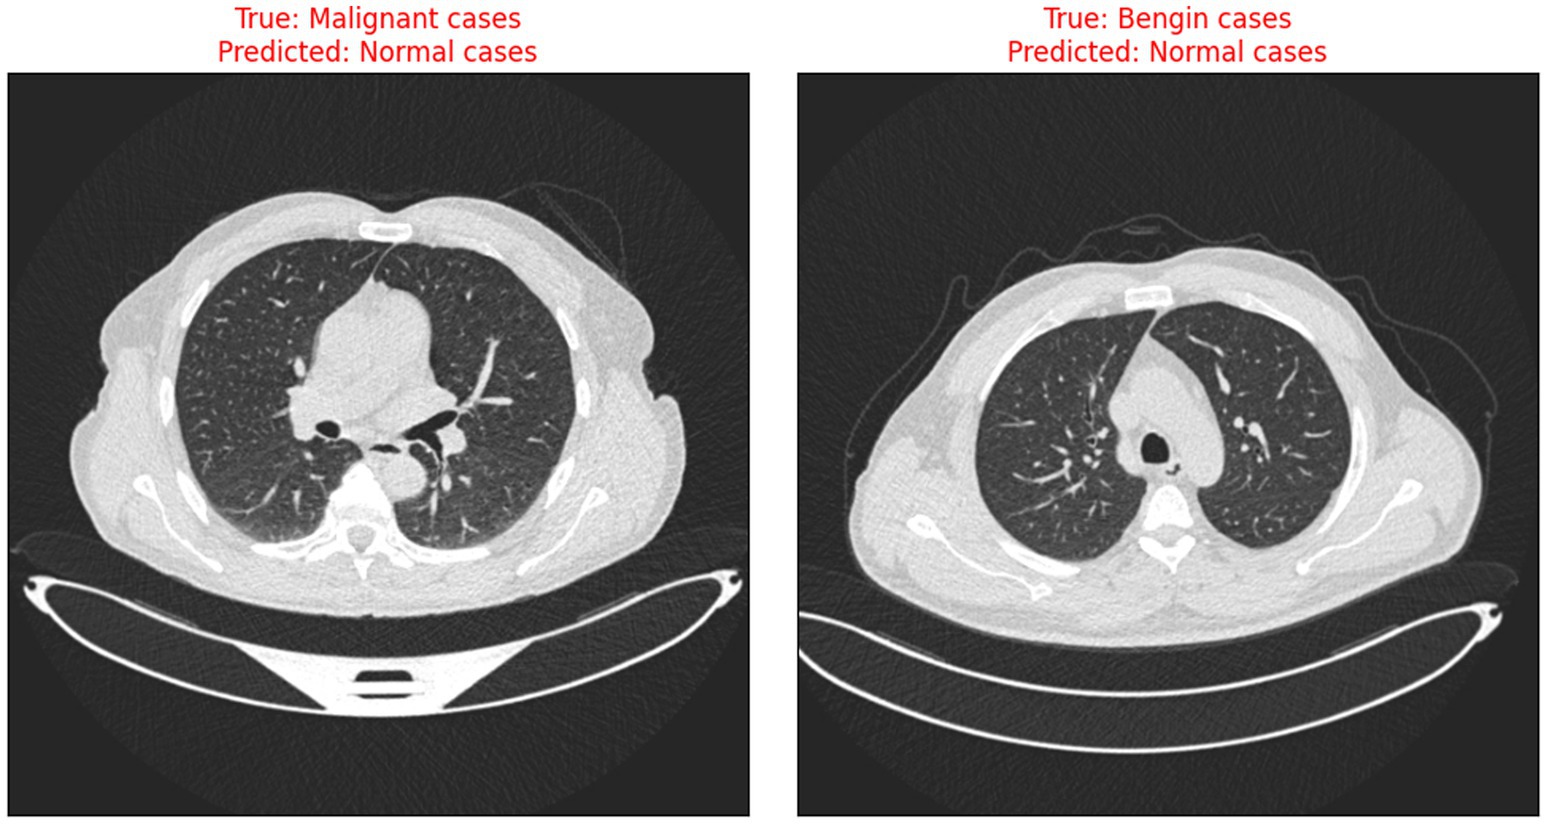

The risks associated with misclassification, particularly false negatives in malignant cases are significant in clinical settings. It is crucial that such tools are used as decision-support systems rather than standalone diagnostic solutions, and that their outputs are always interpreted by qualified clinicians. Transparent reporting of model performance and clear communication of its limitations are essential to minimize patient harm and uphold ethical standards in medical AI. Figure 9 illustrates the instances when the model incorrectly classified benign and malignant cases as normal, thus indicating the need for further improvement in distinguishing between minor differences in CT scan images.

Figure 9

Examples of misclassified CT scans.